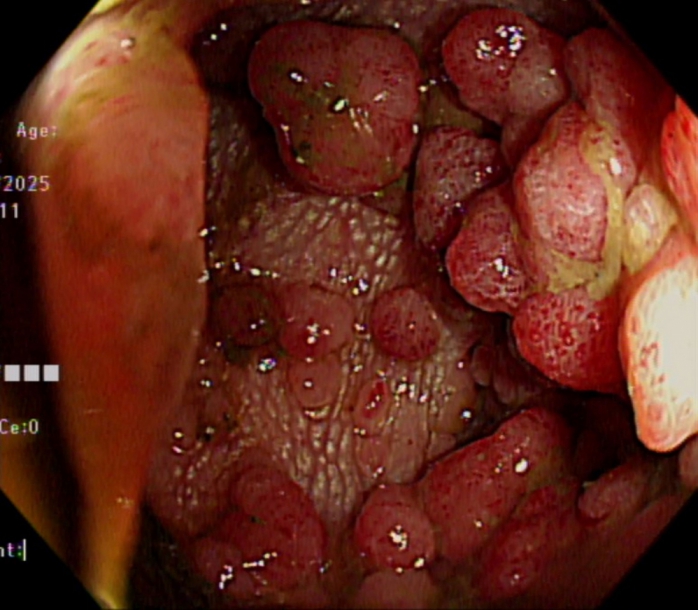

60歲的男性小陳(化名),在30多歲時就確斷為FAP, 做過預防性全大腸切除術,目前都無癌化的狀況,其兒子每幾年都會行大腸鏡檢查,30歲時也發現其大腸內出現數百顆小瘜肉,經醫師建議評估後,也同樣安排預防性全大腸切除術,目前恢復良好。

嘉義基督教醫院大腸直腸科主任朱峻廷醫師表示,FAP是顯性遺傳疾病,只要父母其中一方帶有突變基因,下一代就有50%的機率會遺傳到。根據統計,FAP患者通常在青少年時期就開始出現大腸瘜肉,到了30歲左右,腸道可能布滿上百、上千顆瘜肉,若未治療,90%以上會在中年以前癌化,「只要活得夠久,終其一生幾乎百分之百會演變成大腸癌」。這也是為什麼醫界會不斷強調,一旦家族中有人年輕時就罹患大腸癌或出現大量瘜肉,其他成員必須提高警覺。

另一名40歲的男性小林(化名),在外院行大腸鏡檢查時發現其大腸內出現數百顆大小不一的瘜肉,在等待檢查報告的期間,因腸阻塞被送到嘉基急診,經基因檢測確認罹患了FAP,同時降結腸瘜肉已有癌化跡象並造成腸阻塞;後續進一步檢查又發現小林同時還罹患十二指腸壺腹癌及肝癌,經歷三次手術及多專科團隊的努力,終於將所有的病灶都完整的切除乾淨。